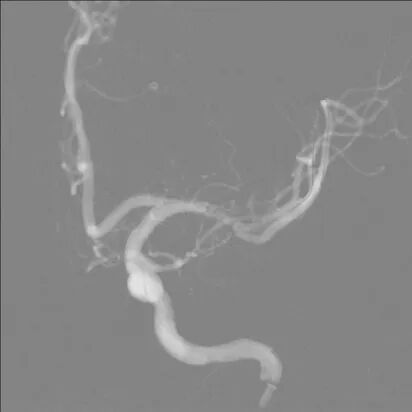

两条Avigo微导丝分别送入左大脑中动脉上下干。

导引导管到位,导丝通过病变

赛诺神畅 颅内球囊扩张导管Neuro RX®2.00*15mm小心通过狭窄段。

球囊通过病变

缓慢扩张球囊,球囊成形好。

球囊扩张过程

扩张后,狭窄稍有改善。

扩张后造影